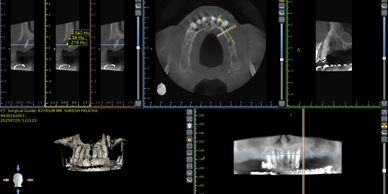

Our state-of-the-art 3Shape scanner and comprehensive imaging systems create precise digital models of your oral anatomy. This allows us to plan implant placement with millimeter accuracy, reducing treatment time and enhancing predictability.